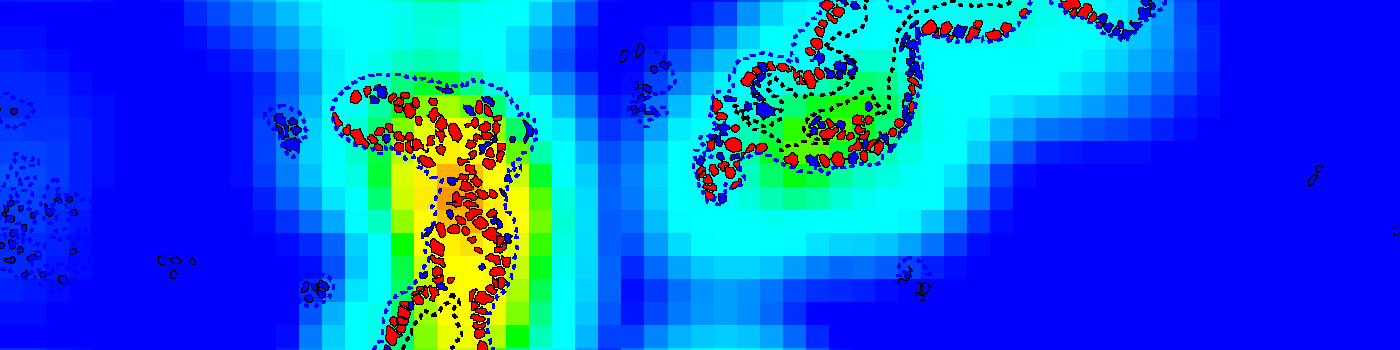

The APP can also be used in a more advanced workflow, including automatic tumor detection and hotspot analysis (Figure 1-5). In this setup, tumor regions are identified automatically from cytokeratin stained slides (e.g. PCK) using the APP “20002 – PCK VDS, Tumor Detection”. The APP “10114 – Hot Spot” is used to generate a heatmap to identify a hot spot containing, e.g. 100 cells and the proliferative index is reported for both the entire tumor region and the hot spot.

Step 4: Load and run the APP 10114 – Hot Spot to visualize the heatmap